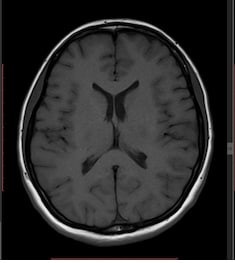

Une chirurgie vous a été proposée. Cette chirurgie a pour but d’évacuer le liquide céphalorachidien (LCR) accumulé dans les ventricules du cerveau vers un autre réservoir (le plus souvent dans le péritoine (ventre)) : dérivation ventriculo-péritonéale. Parfois, le terme shunt peut être employé.